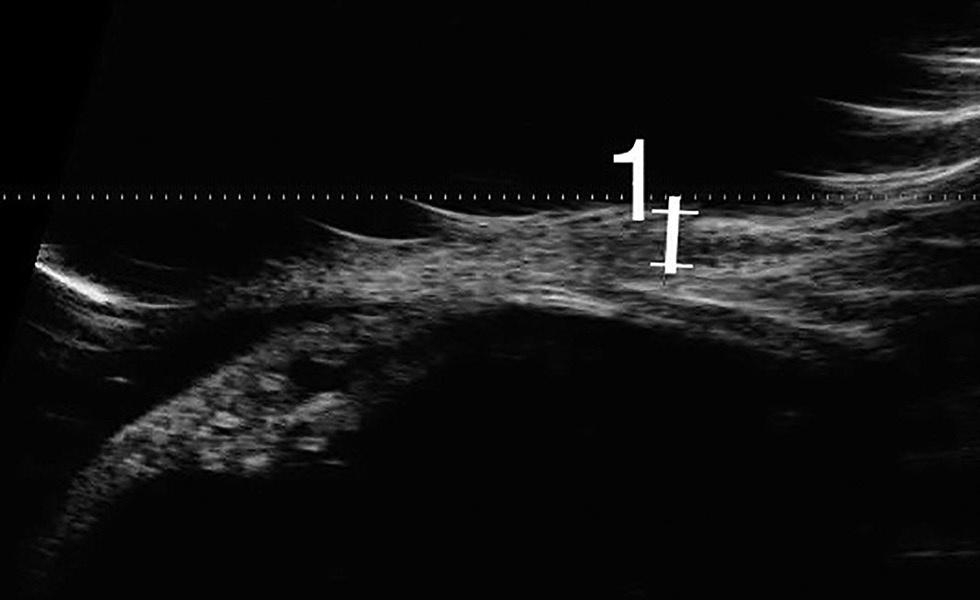

На 21-е сутки после операции в области дефекта определяли блестящую конъюнктиву, отёк и бледность тканей в зоне хирургического вмешательства, а также новообразованные сосуды в направлении к центру дефекта. Область обнажённой склеры не визуализировали, но продолжали определять повышенную плотность и неравномерную толщину конъюнктивы, достигающую 0,5 мм (рис. 3). Толщина конъюнктивы в области дефекта составляет 0,6 мм.

Рис. 3. Ультразвуковая биомикроскопия на 21-е сутки после операции, фаза резорбции слоя клеевой плёнки.

Fig. 3. Ultrasound biomicroscopy on Day 21 post-surgery; phase of the adhesive film resorption.

С помощью УБМ была выявлена фенестрация и резорбция слоя клеевой плёнки, полное закрытие склеры новообразованной конъюнктивой, которая была утолщена до 0,5 мм. По данным ОКТ наблюдалось снижение выраженности проминенции конъюнктивы в области трансплантации относительно здоровых тканей (рис. 4).